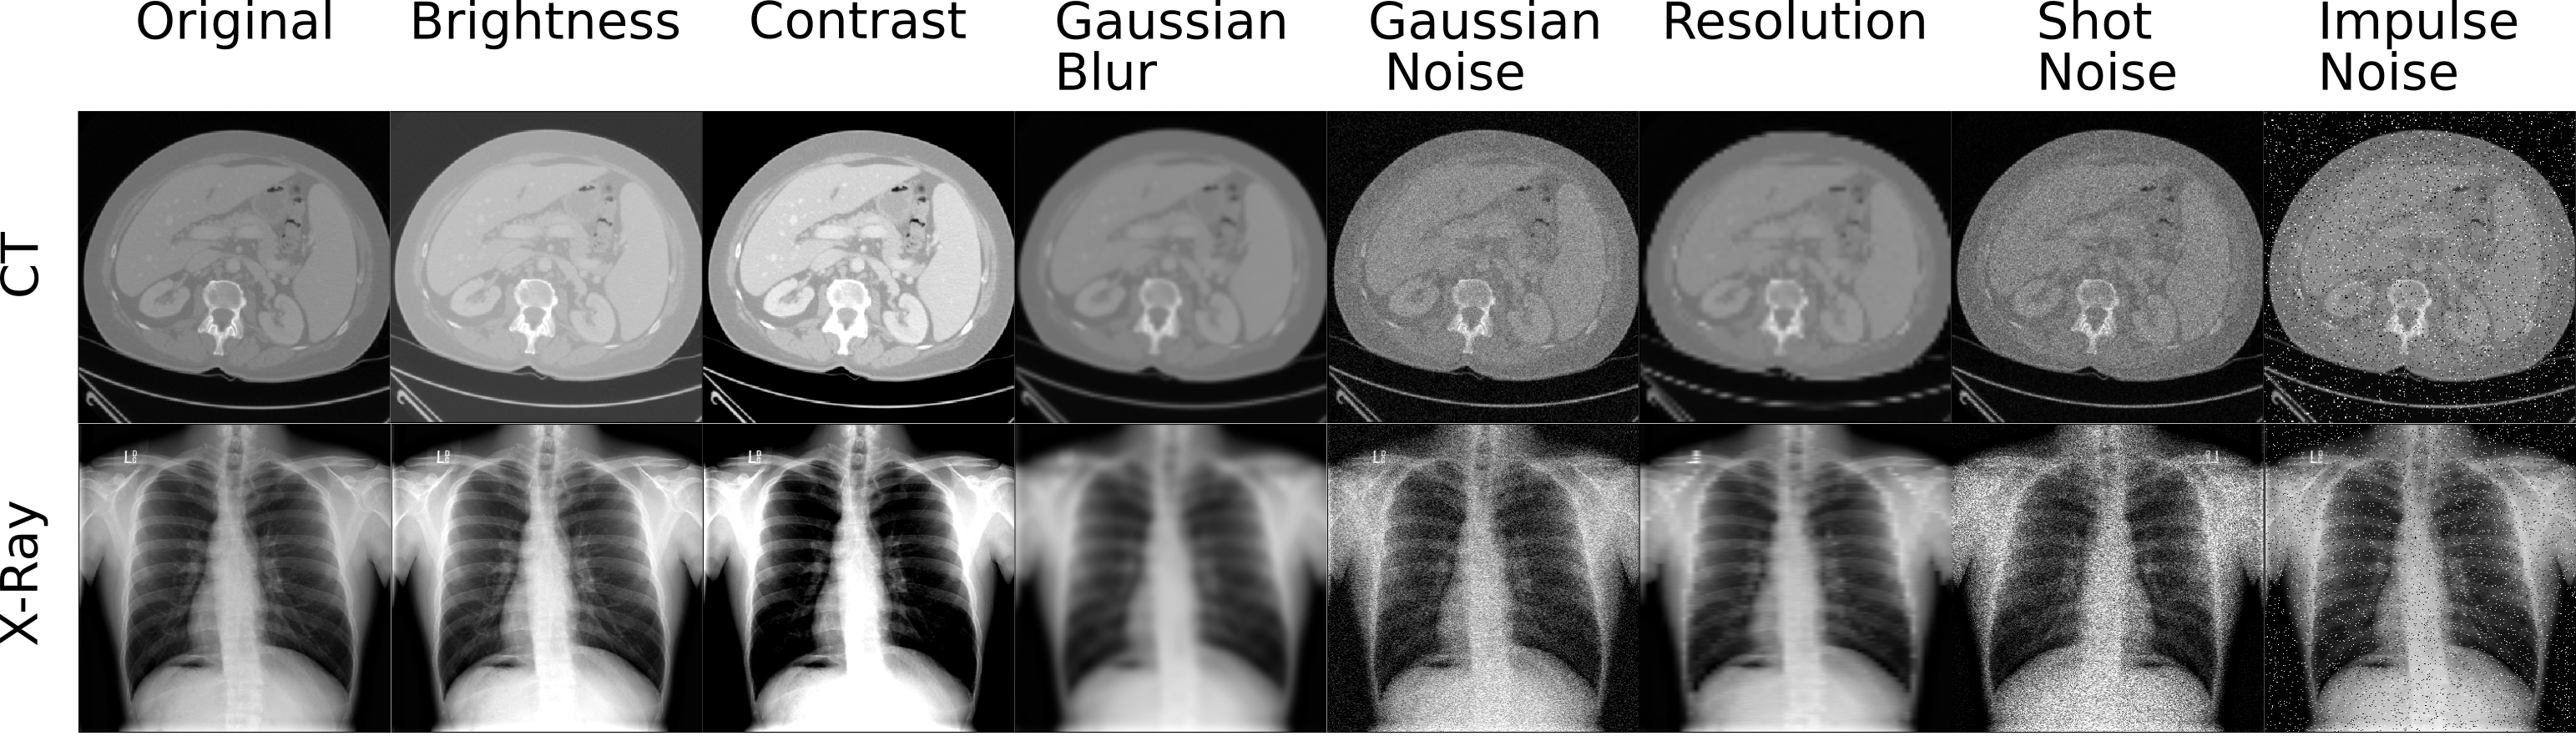

Refer to caption

Figure 1: Examples of image corruptions. The first column shows the original image, while the following columns illustrate different image corruptions. The first row corresponds to a CT image for multi-organ segmentation. The second row shows an example X-ray image for pneumonia detection.

Image Corruptions: Improving robustness to image corruptions was previously studied against adversarial examples [16] and common image corruptions [13]. Although adversarial examples are a good basis to benchmark neural networks, they are not common in real-world applications. Hence, we focus on seven image corruptions commonly encountered during acquisition, shown in Fig. 1. In medical imaging, there is always a trade-off between minimizing radiation doses at the cost of image noise and quality. Examples of such noises include Gaussian noise, shot noise and impulse noise, which are included in our simulated image corruptions. Changes in image appearance are simulated by image contrast and brightness, as a surrogate of contrast enhancement and high exposure. Gaussian blur simulates patient movement during acquisition and resolution refers to data coming from different scanner resolutions.

To address these questions, we evaluate networks trained via fully- and self-supervised learning in the presence of image corruptions. In our experiments, we evaluate a set of seven image corruptions described in the previous section and shown in Fig. 1. For each corruption, we apply five different levels of severity. These levels are found empirically for every image corruption and for every task (classification, segmentation) by keeping the lower bound performance higher than 0.49 using a validation set.